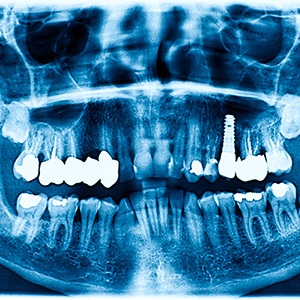

Dental implants refer to small rods made from biocompatible materials like titanium that are surgically placed into a patient’s jawbone. These posts are capable of fusing with the surrounding bone tissue, meaning that they can replace the missing roots of lost teeth – which is something that traditional options like dentures or bridges cannot do. Once this fusion has occurred, a custom-made dental restoration can be attached on top to replace the visible portions of the teeth. However, these restorations aren’t just for sure; thanks to the support from the implant posts, these new teeth are durable, functional, and can serve a patient well for life under the right circumstances.

- Dental Implant Surgery – Dr. Zhang can complete the entire dental implant process here in our office, meaning you won’t have to coordinate with other teams or offices. As for the surgery itself, it’s a very straightforward process. Anywhere from one to a few implants can be used, and after the jaw tissue is accessed through the gums, the posts are placed at precise angles directly into the bone.

- Dental Implant Osseointegration/Abutment – Following the surgery, your mouth will need several months to heal. Osseointegration, or the process in which the posts fuse with your bone tissue, is arguably the most important part of your dental implant journey. You’ll be given guidelines on how to accommodate this process. Afterward, you’ll return to receive your abutments, which go on top of the implant posts and help to secure your restoration(s).

- Delivery of Dental Implant Restoration(s) – Dental implants can be used to replace any number of missing teeth, regardless of where they are located in the mouth. After you’ve received your abutments and we’ve confirmed that your implants have successfully fused with your jaw, you will receive your custom-made restoration, which is attached to your abutments and is supported by the implant posts.